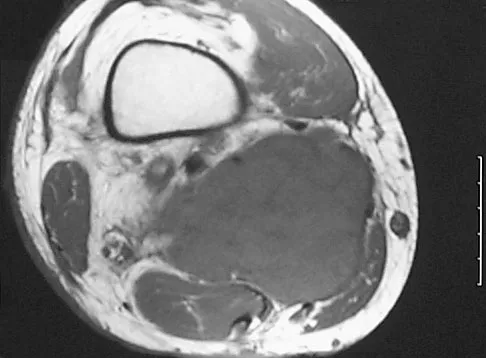

Question 50

Figures 34a through 34c show an axial proton density (spin echo long TR, short TE) image, a sagittal inversion recovery (STIR) image, and a sagittal T1-weighted (short TR, short TE) image of the left thigh. What is the most likely diagnosis?

Explanation